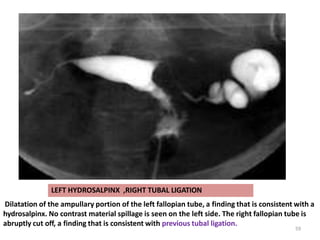

Dilatation of the ampullary portion of the left fallopian tube, a finding that is consistent with a

hydrosalpinx. No contrast material spillage is seen on the left side. The right fallopian tube is

abruptly cut off, a finding that is consistent with previous tubal ligation.

LEFT HYDROSALPINX ,RIGHT TUBAL LIGATION